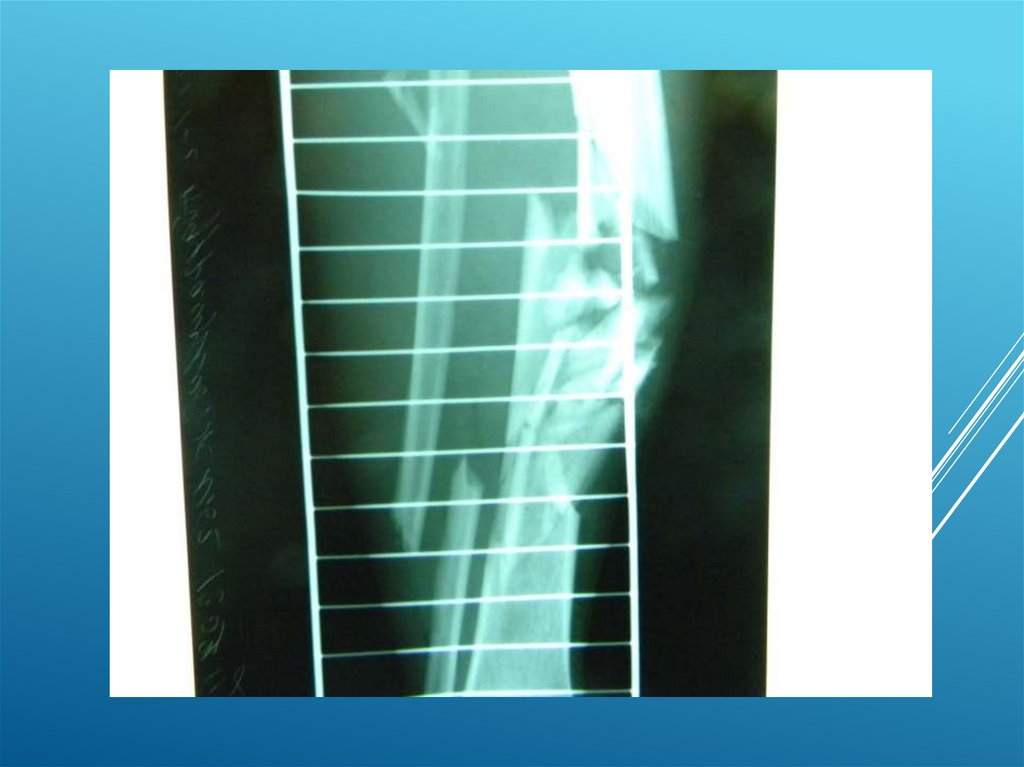

Клинические примеры:

Пациент Д. 32 года

8.

9.

10.

11.

12.

13.